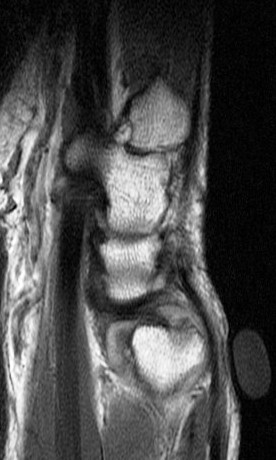

Ulnar impingement syndrome